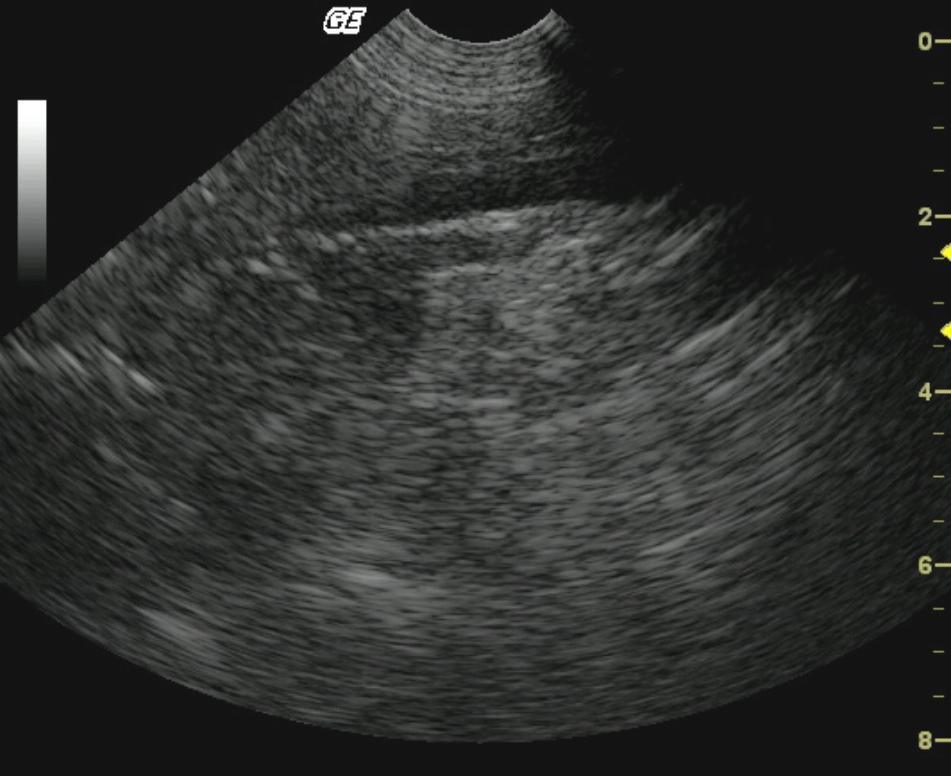

A 5-year-old FS Pit Bull Terrier dog presented for not acting right per owner, vomiting for one day, and anorexia. Temperature was normal. Initial blood chemistry revealed azotemia, low cholesterol, hyperamylasemia, and low triglycerides. CBC found thrombocytopenia. Total T4 and Pancreatic Lipase Immunoreactivity were both normal. Within a few weeks, the patient was examined again due to a decreased appetite, decreased drinking, diarrhea, several episodes of vomiting, and the possibility of toxin exposure. The dog was then admitted to the hospital for I.V. fluid therapy, blood work, urinalysis, ACTH stim., and abdominal ultrasound. Physical exam found patient weak with a doughy abdomen, depressed mentation, slight tachycardia with thready pulses, tacky mucous membranes, and five pounds of weight loss in 1.5 months. Recheck blood chemistry revealed hypoglycemia, azotemia, hyperkalemia, and hyperamylasemia. CBC was within normal limits. Urinalysis showed a normal pH and specific gravity. Hypoadrenocorticism was diagnosed on the ACTH stimulation test.